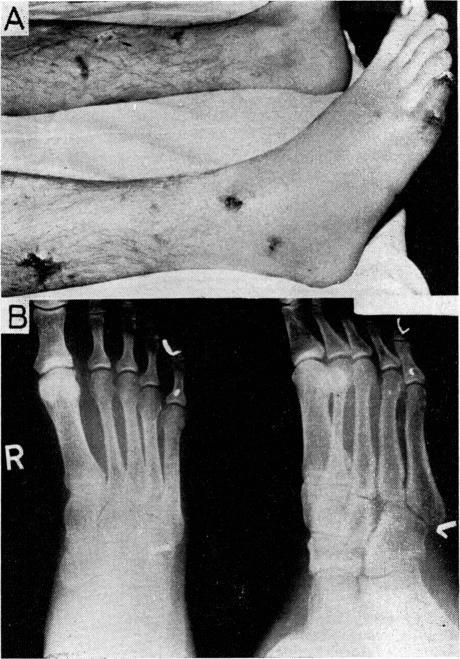

Missile wounds, Belfast 1971.